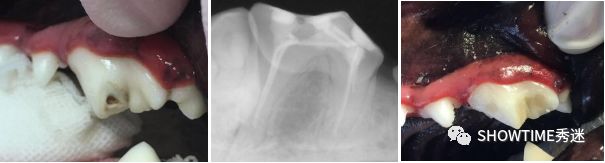

另一种是根管治疗术,其实跟人的“抽牙神经”治疗是一样的,治疗过程需要开髓、拔髓、根治制备、根管干燥、根管填充及根管封盖等,不过根管治疗主要适用于严重感染且不可复牙髓炎的恒牙或已有牙根尖周炎的恒牙。

臼齿的根管治疗手术前后

复杂齿折的手术治疗因为手术流程复杂,涉及细节非常多, 建议粑粑麻麻们一定要选择专业的宠物牙科医师来给宝贝们进行这类牙科手术,以免手术失败,引起了诸如根管或牙根尖穿孔、感染等严重并发症。